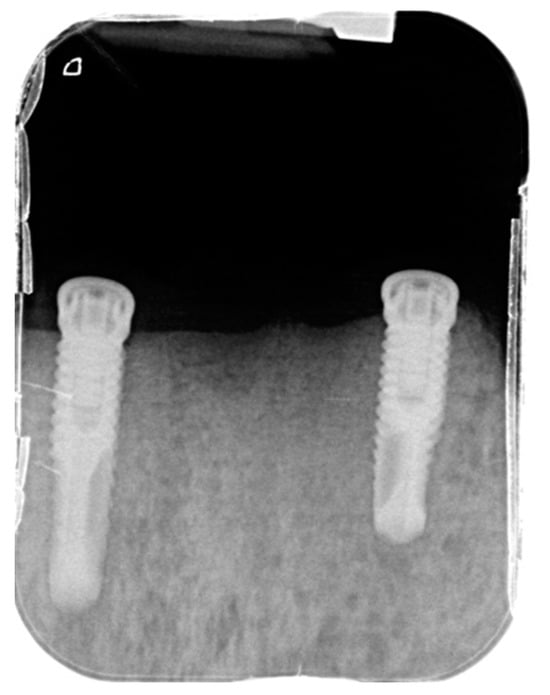

2.1.1. Surgery Appointment (September 2021)

- surgical insertion of two anterior implants in the region of the mandibular canines